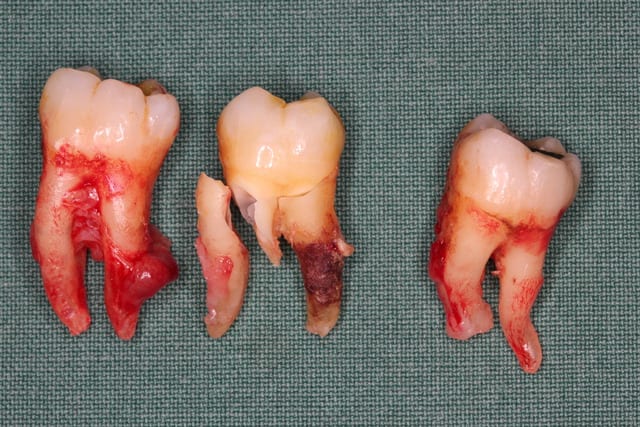

1.Bon... situation pré-extractionelle ( Je crois qu il faillait vraiment extraire )

On a fait les PRfs et extractions des molaires maxillaires voici un mois

Et on vient d extraire le molaires inf avec PRFs ce jour

PS2 Message pour Olivier : quel traitement paro fais tu à cette patiente qd tu vois les pièces extractionnelles ?????